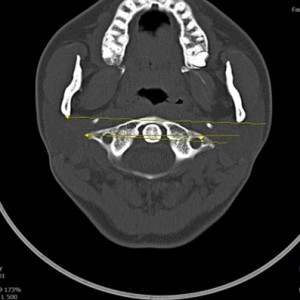

안면 두개골 엑스레이 검사

Submento Vertex View 포함

안면 두개골 CT

경추 1,2번의 변위 파악

턱의 소리가 오래되지 않아서 근육의 긴장만 있는 경우 치료 후 소리의 감소가 빠른 편이나 인대의 문제일 경우 턱의 위치를 교정후 인대를 강화하는 치료를 추가적으로 해서 더 줄일수 있습니다. 디스크가 닳아버린 문제라면 치료후에도 소리가 남을수 있습니다. CT와 초음파등의 영상진단을 통해 치료 예후와 경과를 확인 가능합니다.